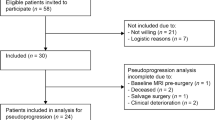

Two studies (study A and B) were performed in this prospective trial, which was approved by the local medical ethics committee. Patients were asked to participate by their treating physician and informed consent was obtained.

In study A, we included patients treated with radiotherapy in combination with concomitant and six cycles adjuvant TMZ for newly diagnosed GBM. The treatment evaluation of these patients consisted of MRI and 201Tl SPECT postoperatively, i.e., prior to the concomitant phase (baseline), and prior to the adjuvant phase. Thereafter, additional MRI was performed after three and six courses and 201Tl SPECT after three adjuvant TMZ courses (flowchart interventions imaging, see Table 1).

Study B, comprised patients treated with TMZ for recurrent glioma. The treatment evaluation of these patients consisted of MRI and 201Tl SPECT prior to chemotherapy (baseline), and additional MRI after three, six, and nine courses, and 201Tl SPECT after three and nine TMZ courses (Table 1).

From September 2004 to October 2008, 46 patients treated with TMZ in our institution were included: 24 patients for study A and 22 patients for study B. Patient characteristics and outcomes are shown in Table 2.

In study A, tumor histology was GBM, except for one patient with an astrocytoma (grade II), who had undergone surgery 1 year before, and started with TMZ chemoradiotherapy under the suspicion of tumor progression and dedifferentiation to a GBM. All GBM patients were operated on recently, and underwent standard focal fractionated radiotherapy (60 Gy) in combination with concomitant TMZ chemotherapy (75 mg/m2 daily during radiotherapy). After a 4-week interval, adjuvant TMZ treatment was given on a standard schedule (150–200 mg/m2 daily for 5 days, repeated every 28 days; six courses). All patients were chemonaive. Two patients did not receive adjuvant TMZ as a result of persistent myelosuppression. Eighty-one MRI and 65 201Tl SPECT scans were performed. The median interval between baseline imaging and start of chemoradiotherapy was 6 days. The median OS was 15 months, and the median (clinical) progression-free survival (PFS) was 9 months. Ten out of 24 patients had not died as of October 2008, two of which had already shown tumor progression. Survival data of these patients were censored at this date.

In study B, initial tumor histologies included GBM (n = 8), astrocytoma, (n = 6), anaplastic astrocytoma (n = 3), oligodendroglioma (n = 2), anaplastic oligodendroglioma (n = 2), and oligoastrocytoma (n = 1). Because of the heterogeneity of histology in this relatively small patient group, histology was dichotomised (GBM versus non-GBM). All patients had previously undergone craniotomy and 20 out of 22 irradiation. The median interval between initial glioma therapy and start of TMZ chemotherapy for recurrent disease was 33 (range, 4–187) months. Pathological verification of recurrent disease was obtained in 13 of 22 patients (seven GBMs versus six non-GBMs). TMZ was given on a standard schedule (150–200 mg/m2 daily for 5 days, repeated every 28 days). Fifty-seven MRIs and 48 201Tl SPECTs were performed. The median interval between baseline imaging and start of chemotherapy was 7 days. The median OS and PFS were 10 and 5 months, respectively. Six out of 22 patients had neither shown tumor progression nor had died as of October 2008. Survival data of these patients were censored at this date.